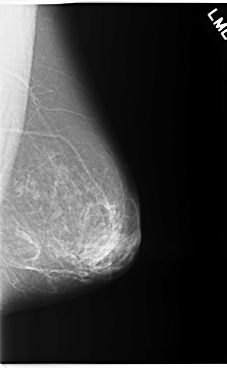

C_0255_1.LEFT_MLO

LEFT_MLO LINES 5880 PIXELS_PER_LINE 3624 BITS_PER_PIXEL 12 RESOLUTION 50 NON_OVERLAY